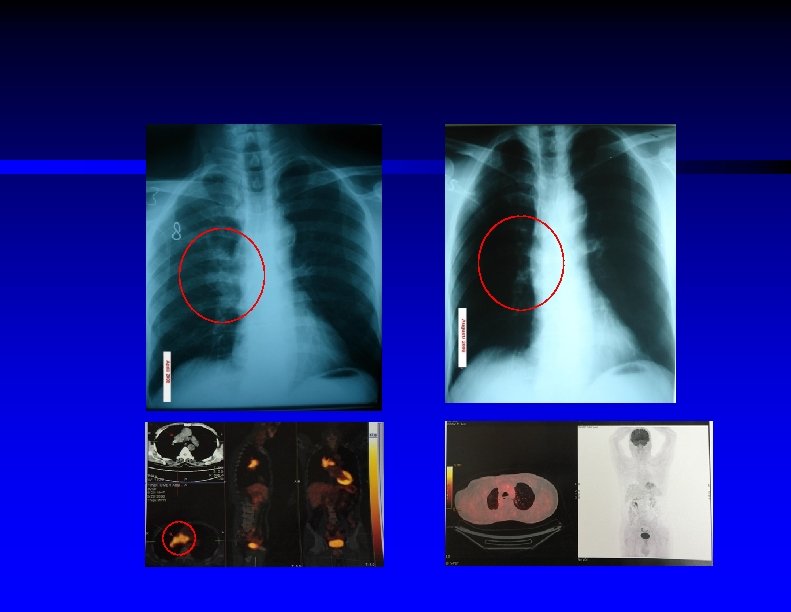

Investigation Ø Whole body PET/CT scan

Metastatic breast cancer to liver After 3 cycles of chemotherapy (21 days dosing schedule)